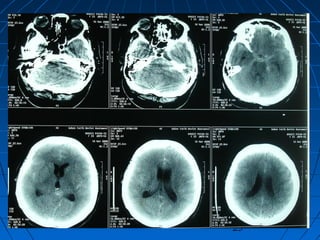

SPONTAN İNTRAPARENKİMALSPONTAN İNTRAPARENKİMAL

HEMORAJİHEMORAJİ

GENEL BİLGİLERGENEL BİLGİLER

 Nöral parenkim dokusu içineNöral parenkim dokusu içine

kanama,kanama,

 Tüm strokların % 10’uTüm strokların % 10’u

 Sıklık yılda yüzbin kişide 12 - 15Sıklık yılda yüzbin kişide 12 - 15

olguolgu

 Her yaşta görülebilir ancakHer yaşta görülebilir ancak 80 y<80 y<

25 kez fazla25 kez fazla

 Geçirilmiş bir CVAGeçirilmiş bir CVA varsa risk çokvarsa risk çok

SPONTAN İNTRAPARENKİMAL HEMORAJİSPONTAN İNTRAPARENKİMAL HEMORAJİ

ETYOLOJİETYOLOJİ

 HipertansiyonHipertansiyon

 Serebral kan akımınınSerebral kan akımının

ani artışıani artışı

 Vasküler anomalilerVasküler anomaliler

 ArteriopatilerArteriopatiler

 TümörlerTümörler

 Kanama diyateziKanama diyatezi

 EnfeksiyonEnfeksiyon

 Dural venöz trombozDural venöz tromboz

 İlaç kullanımıİlaç kullanımı

 EklampsiEklampsi

PATOLOJİPATOLOJİ

 Lentikülostriat, talamoperforanLentikülostriat, talamoperforan

ve baziler arter paramedianve baziler arter paramedian

dallarındakidallarındaki Charcot - BouchardCharcot - Bouchard

anevrizmalarıanevrizmaları

 Amiloid anjiopatiAmiloid anjiopati

 Hemorajik tümörlerHemorajik tümörler

KLİNİKKLİNİK

 Ani başlangıçAni başlangıç

 Bilinç yitimi - nörolojikBilinç yitimi - nörolojik

defisitdefisit

 KusmaKusma

 KİBASKİBAS semptomlarısemptomları

 Yerleşim yerleri :Yerleşim yerleri :

• Bazal ganglionlarBazal ganglionlar

% 37% 37

• TemporalTemporal %%

2020